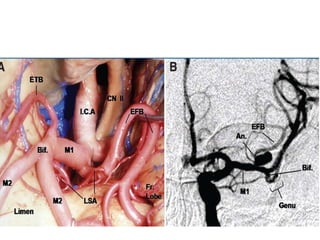

M1 segment

• Microneurosurgical and

angiographic

• Prebifurcation and post

bifurcation parts

• How to distinguish between early

branches and M1

M1 segment • Microneurosurgicaland angiographic • Prebifurcation and post bifurcation parts • How to distinguish between early branches and M1